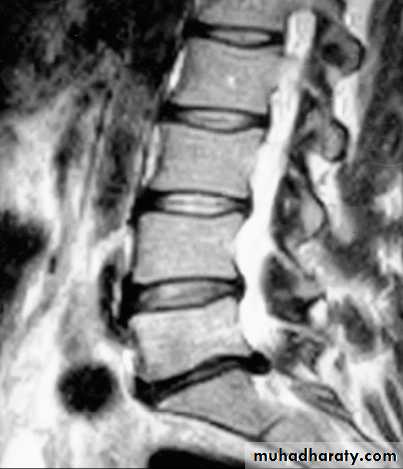

Plain X-rays of the lumbar spine are of little value in the diagnosis of lumbar disc disease, although they may show other conditions such as malignant infiltration of a vertebral body. CT, especially using spiral scanning techniques, can provide helpful images of the disc protrusion and/or narrowing of the exit foramina. MRI is the investigation of choice if available, since soft tissues are well imaged.

L5–SI disc herniationto the left, displacing the SI nerve root

nerve disease